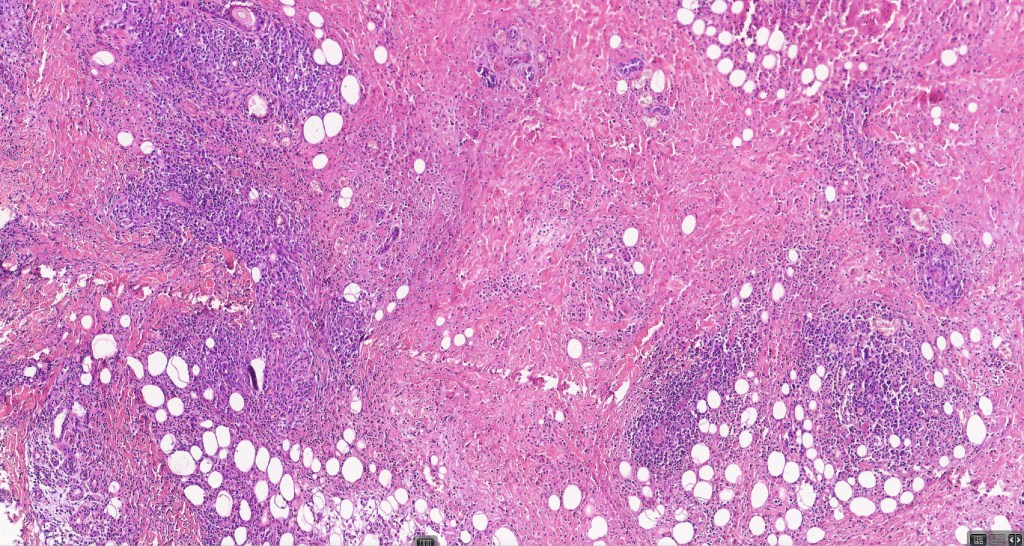

•Type A: 75-80%, wedge shaped infiltrate with base uppermost, large, anaplastic cells with abundant cytoplasm and vesicular nuclei containing prominent nucleoli, can resemble Reed-Sternberg cells, conspicuous mitoses & background infiltrate of lymphocytes, plasma cells, histiocytes, neutrophils & eosinophils

•Mixed variants are not uncommon

•Variable epidermal necrosis, epidermotropism, edema, hemorrhage & vasculitis/thrombosis